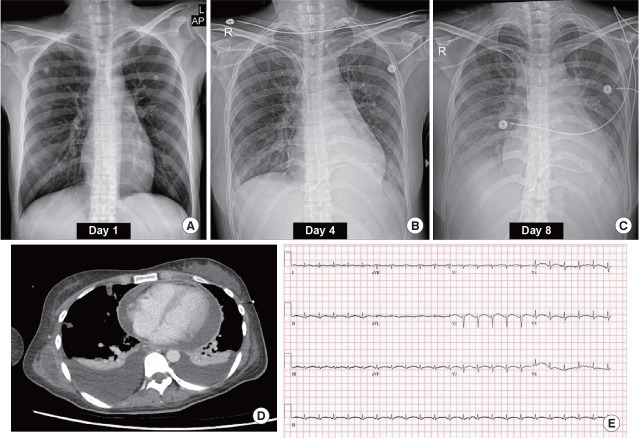

Abstract Image